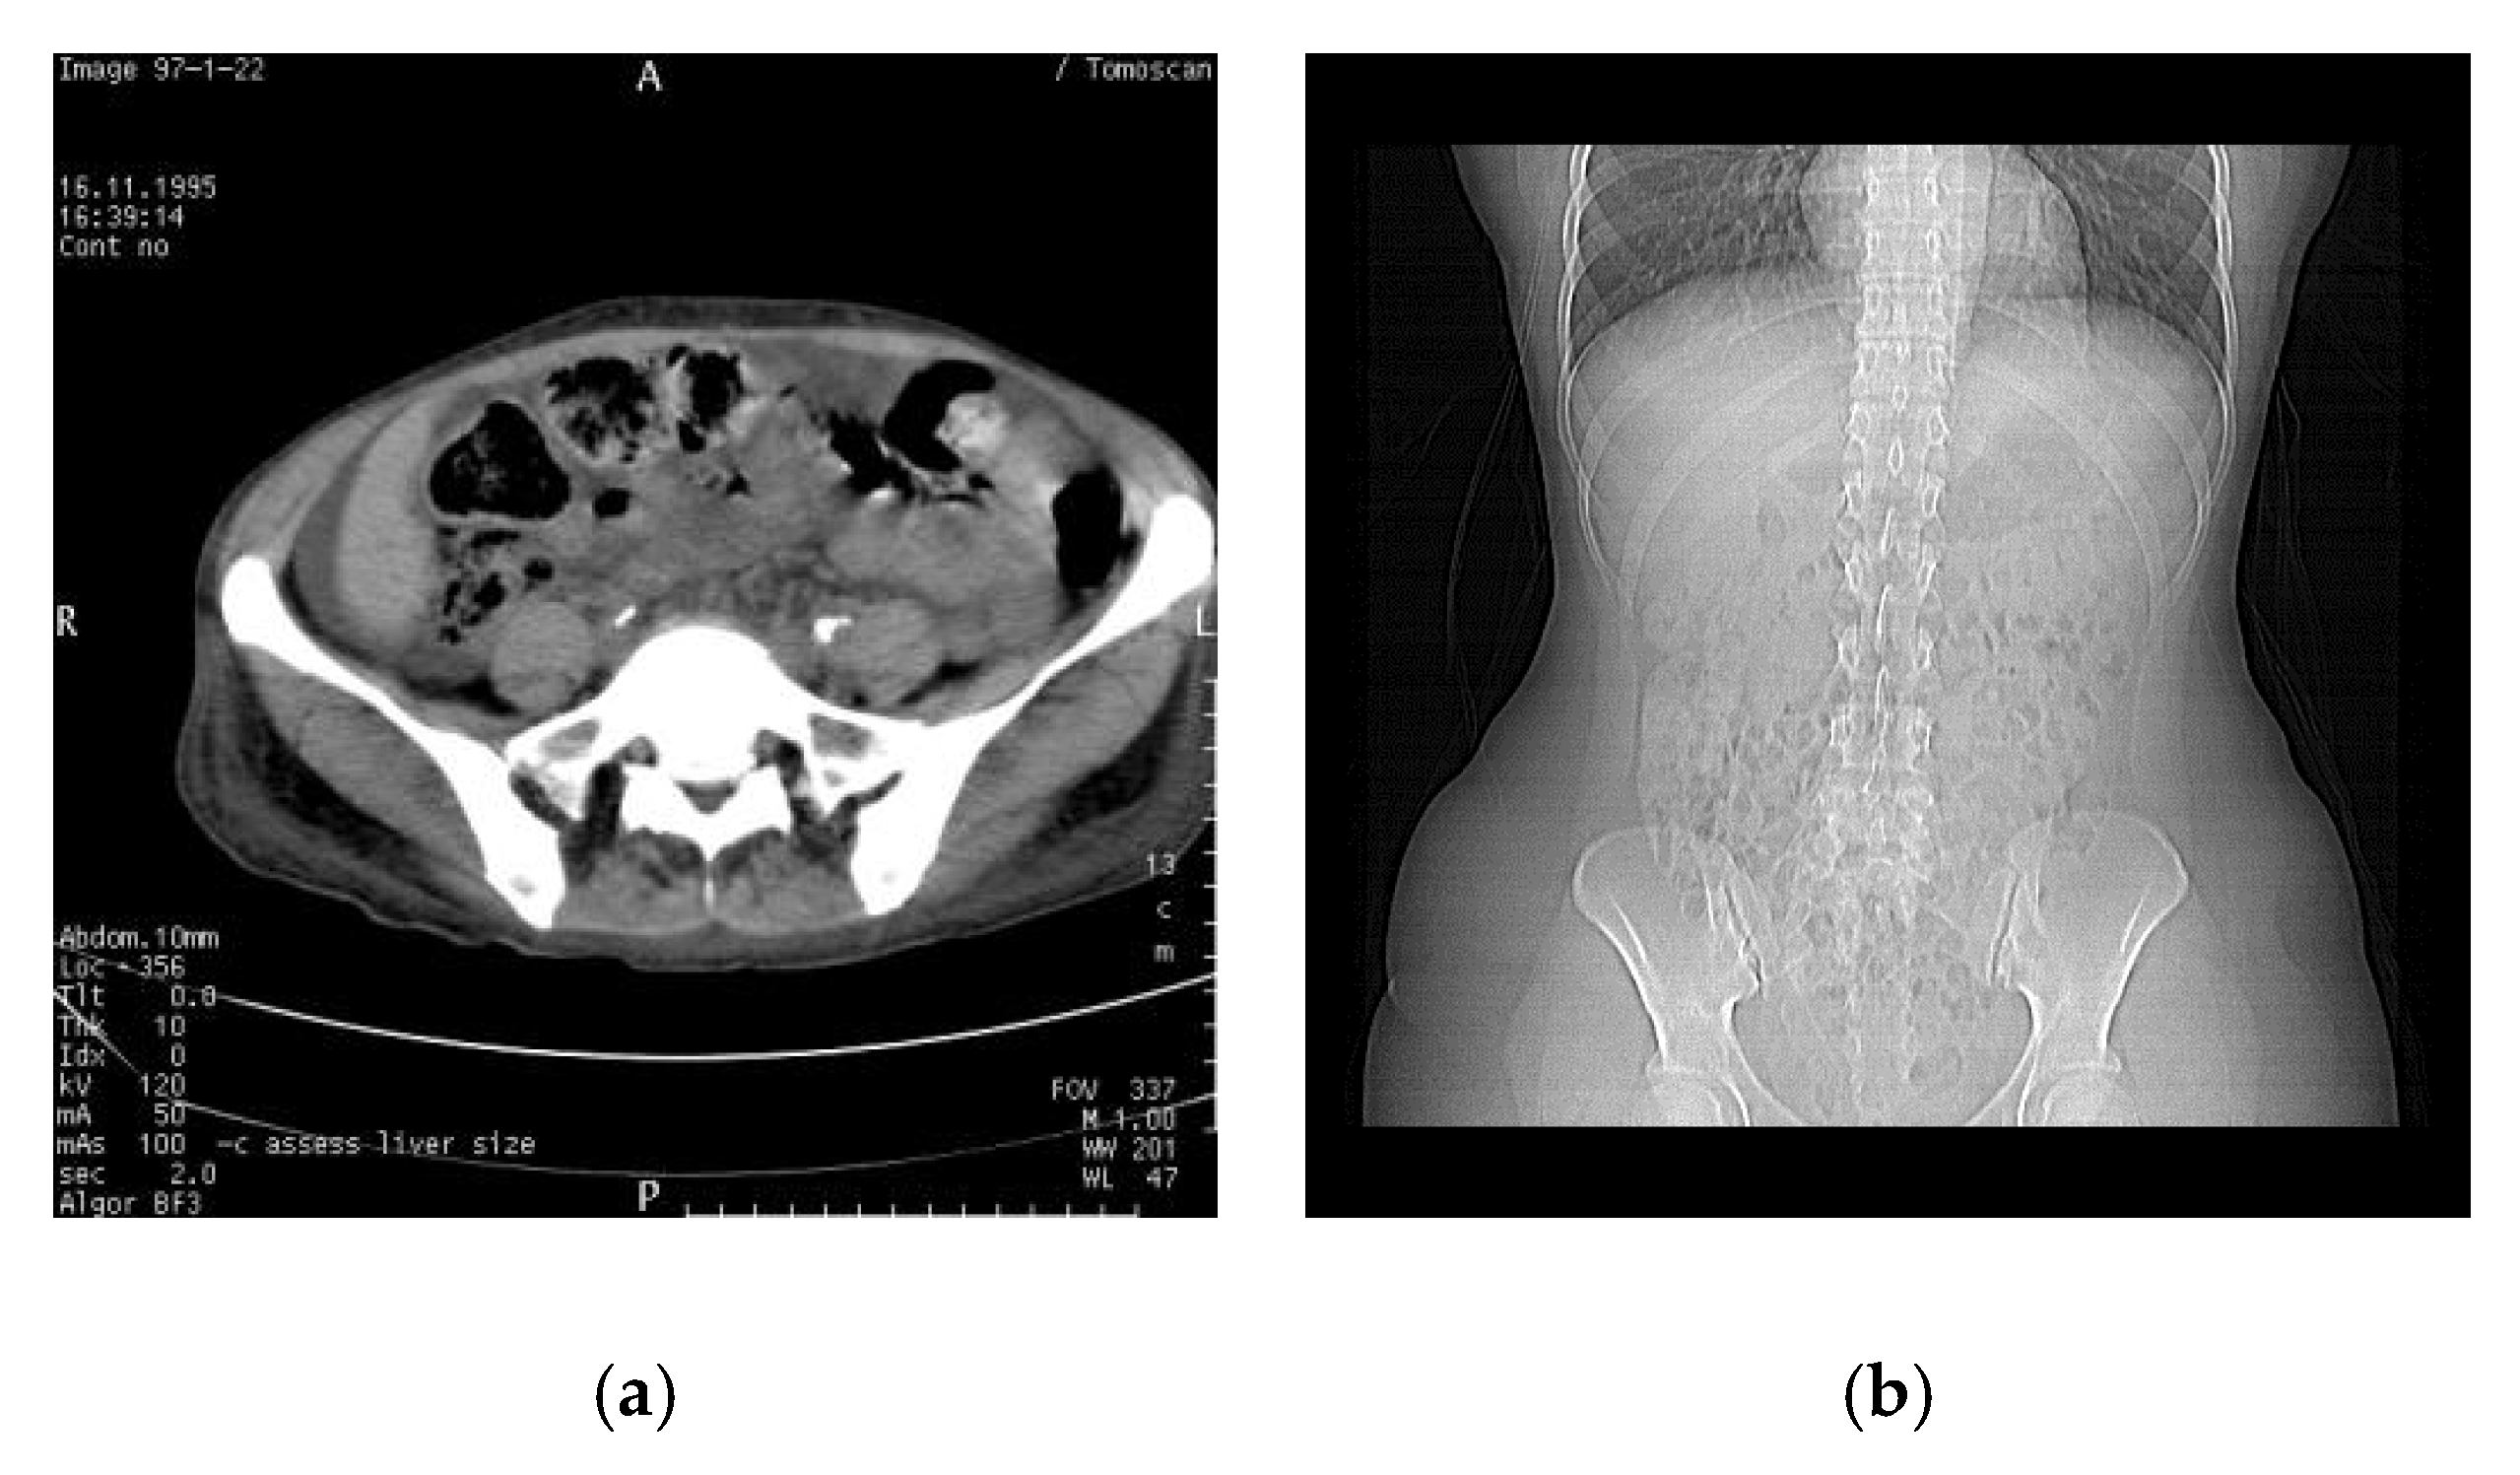

In this section, we show the actual simulation results of WMNet in the ownership authentication verification phase. Figure 4 shows the medical images used in the simulation, which are of size 512 × 512 pixels. The medical images are computed tomography (CT) and X-ray images. Figure 5 shows the watermarks used in the simulation, which are binary images of sizes 64 × 64 and 32 × 32 , respectively. Figure 6 shows the simulated result using Fan’s lossless watermarking system [15] with no imaging processing damage done to the medical images by the proposed system. Figure 6a,b show the 128 × 128 OSI and MSI generated from the 128 × 128 CT image, and Figure 6c shows the extracted watermarks. Figure 6d,e show the 128 × 128 OSI and MSI generated from the X-ray image, and Figure 6f shows the extracted watermarks. From the simulation results, we can see that the lossless watermarking system can correctly retrieve the watermark if the image has not been attacked by image-processing methods.

Figure 4. Medical images used in the experiment. (a) Computed tomography (CT) and (b) X-ray.

Electronics 10 00932 g004